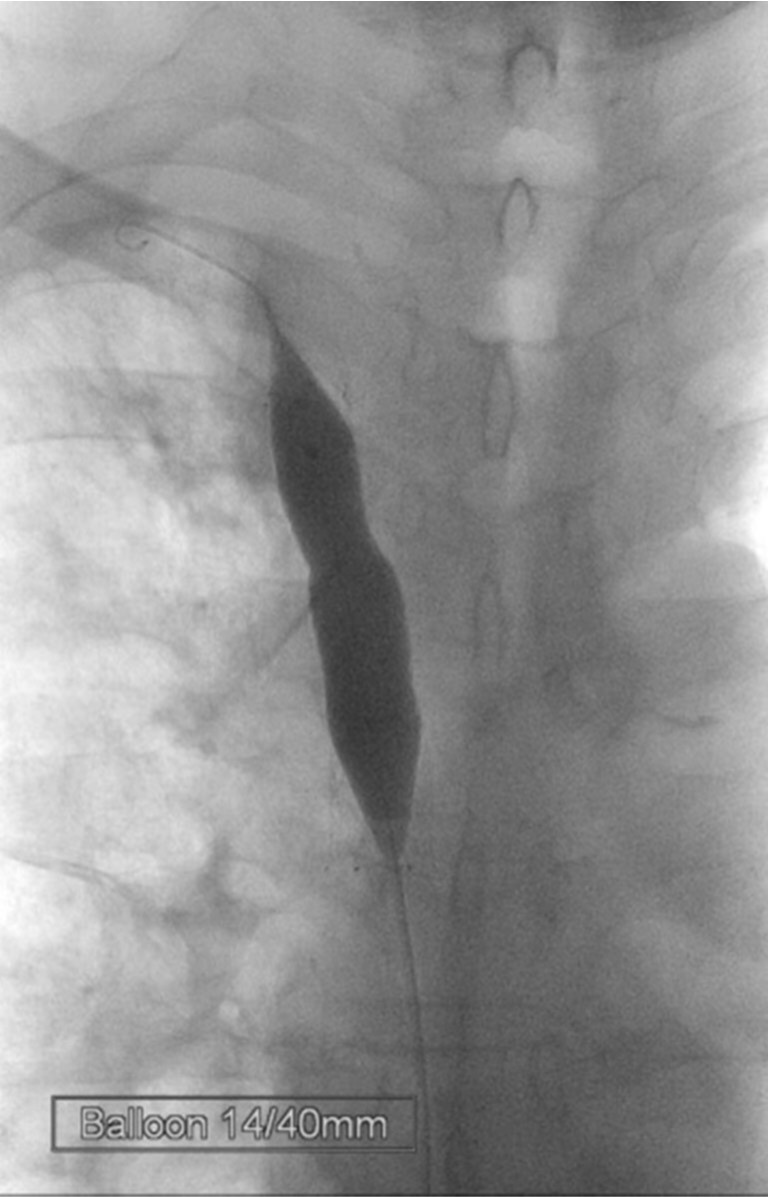

Fig. 4.

Fig. 4. After placing the self-expanding stent, the stenotic segment was dilated with a balloon catheter.